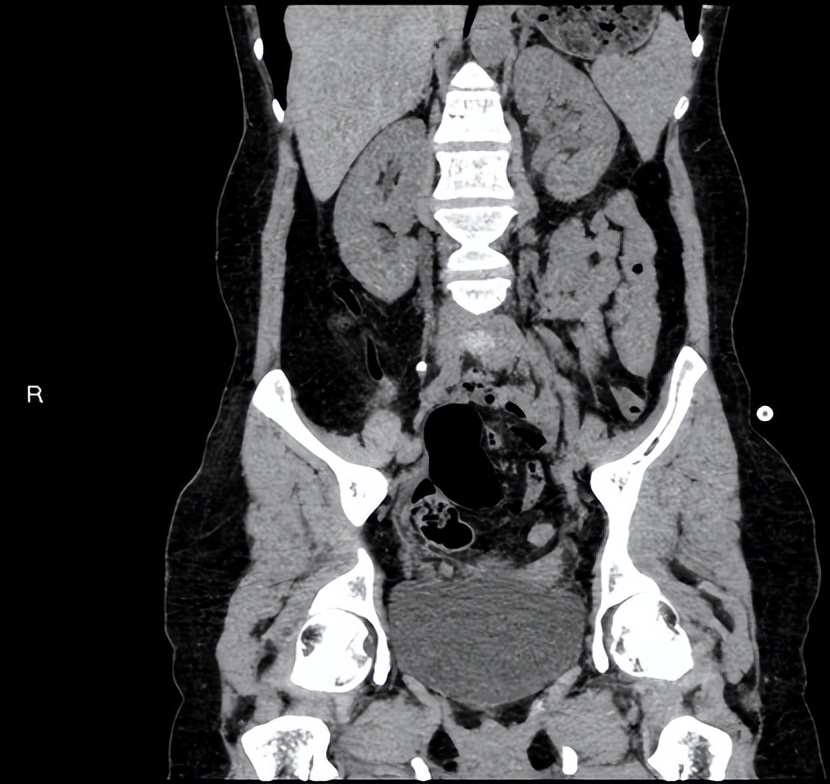

王春阳教授详细了解刘女士的病史,患者左侧输尿管全程扩张,左肾功能轻度受损,右肾积水,右肾功能未见异常,输尿管与膀胱连续性中断并且盆腔有液性暗区。

图一 术前泌尿系三维CT 图二 术后3天泌尿系三维CT